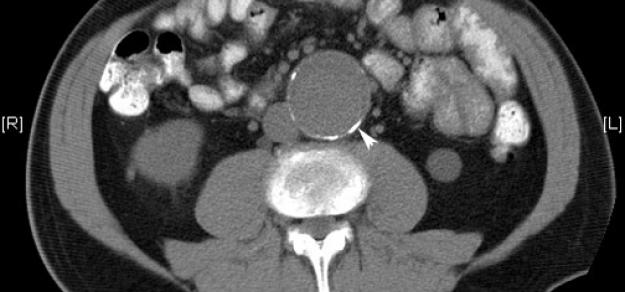

Prescripción de metformina y aneurisma aórtico

Heart, 1 de abril de 2019 la prescripción de metformina podría limitar la expansión de la AAA entre los pacientes con esta enfermedad, y podría estar involucrada con una menor incidencia de aneurisma aórtico y eventos de aneurisma aórtico